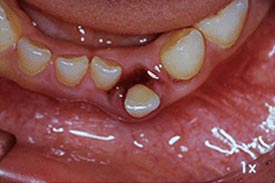

▲永久歯の前歯がガタガタ

(乱ぐい歯)になった様子